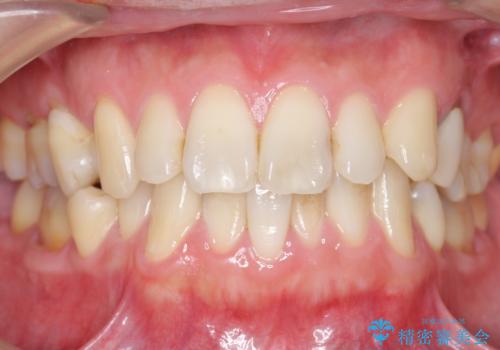

セラミッククラウンにより、抜歯した部分のスペースを閉じ歯並びを整えました。

矯正装置を用いることなくセラミッククラウンにより歯並びを整えスペースを閉じることができ、大変ご満足頂けました。

クラウンの種類:オールセラミッククラウン スタンダード